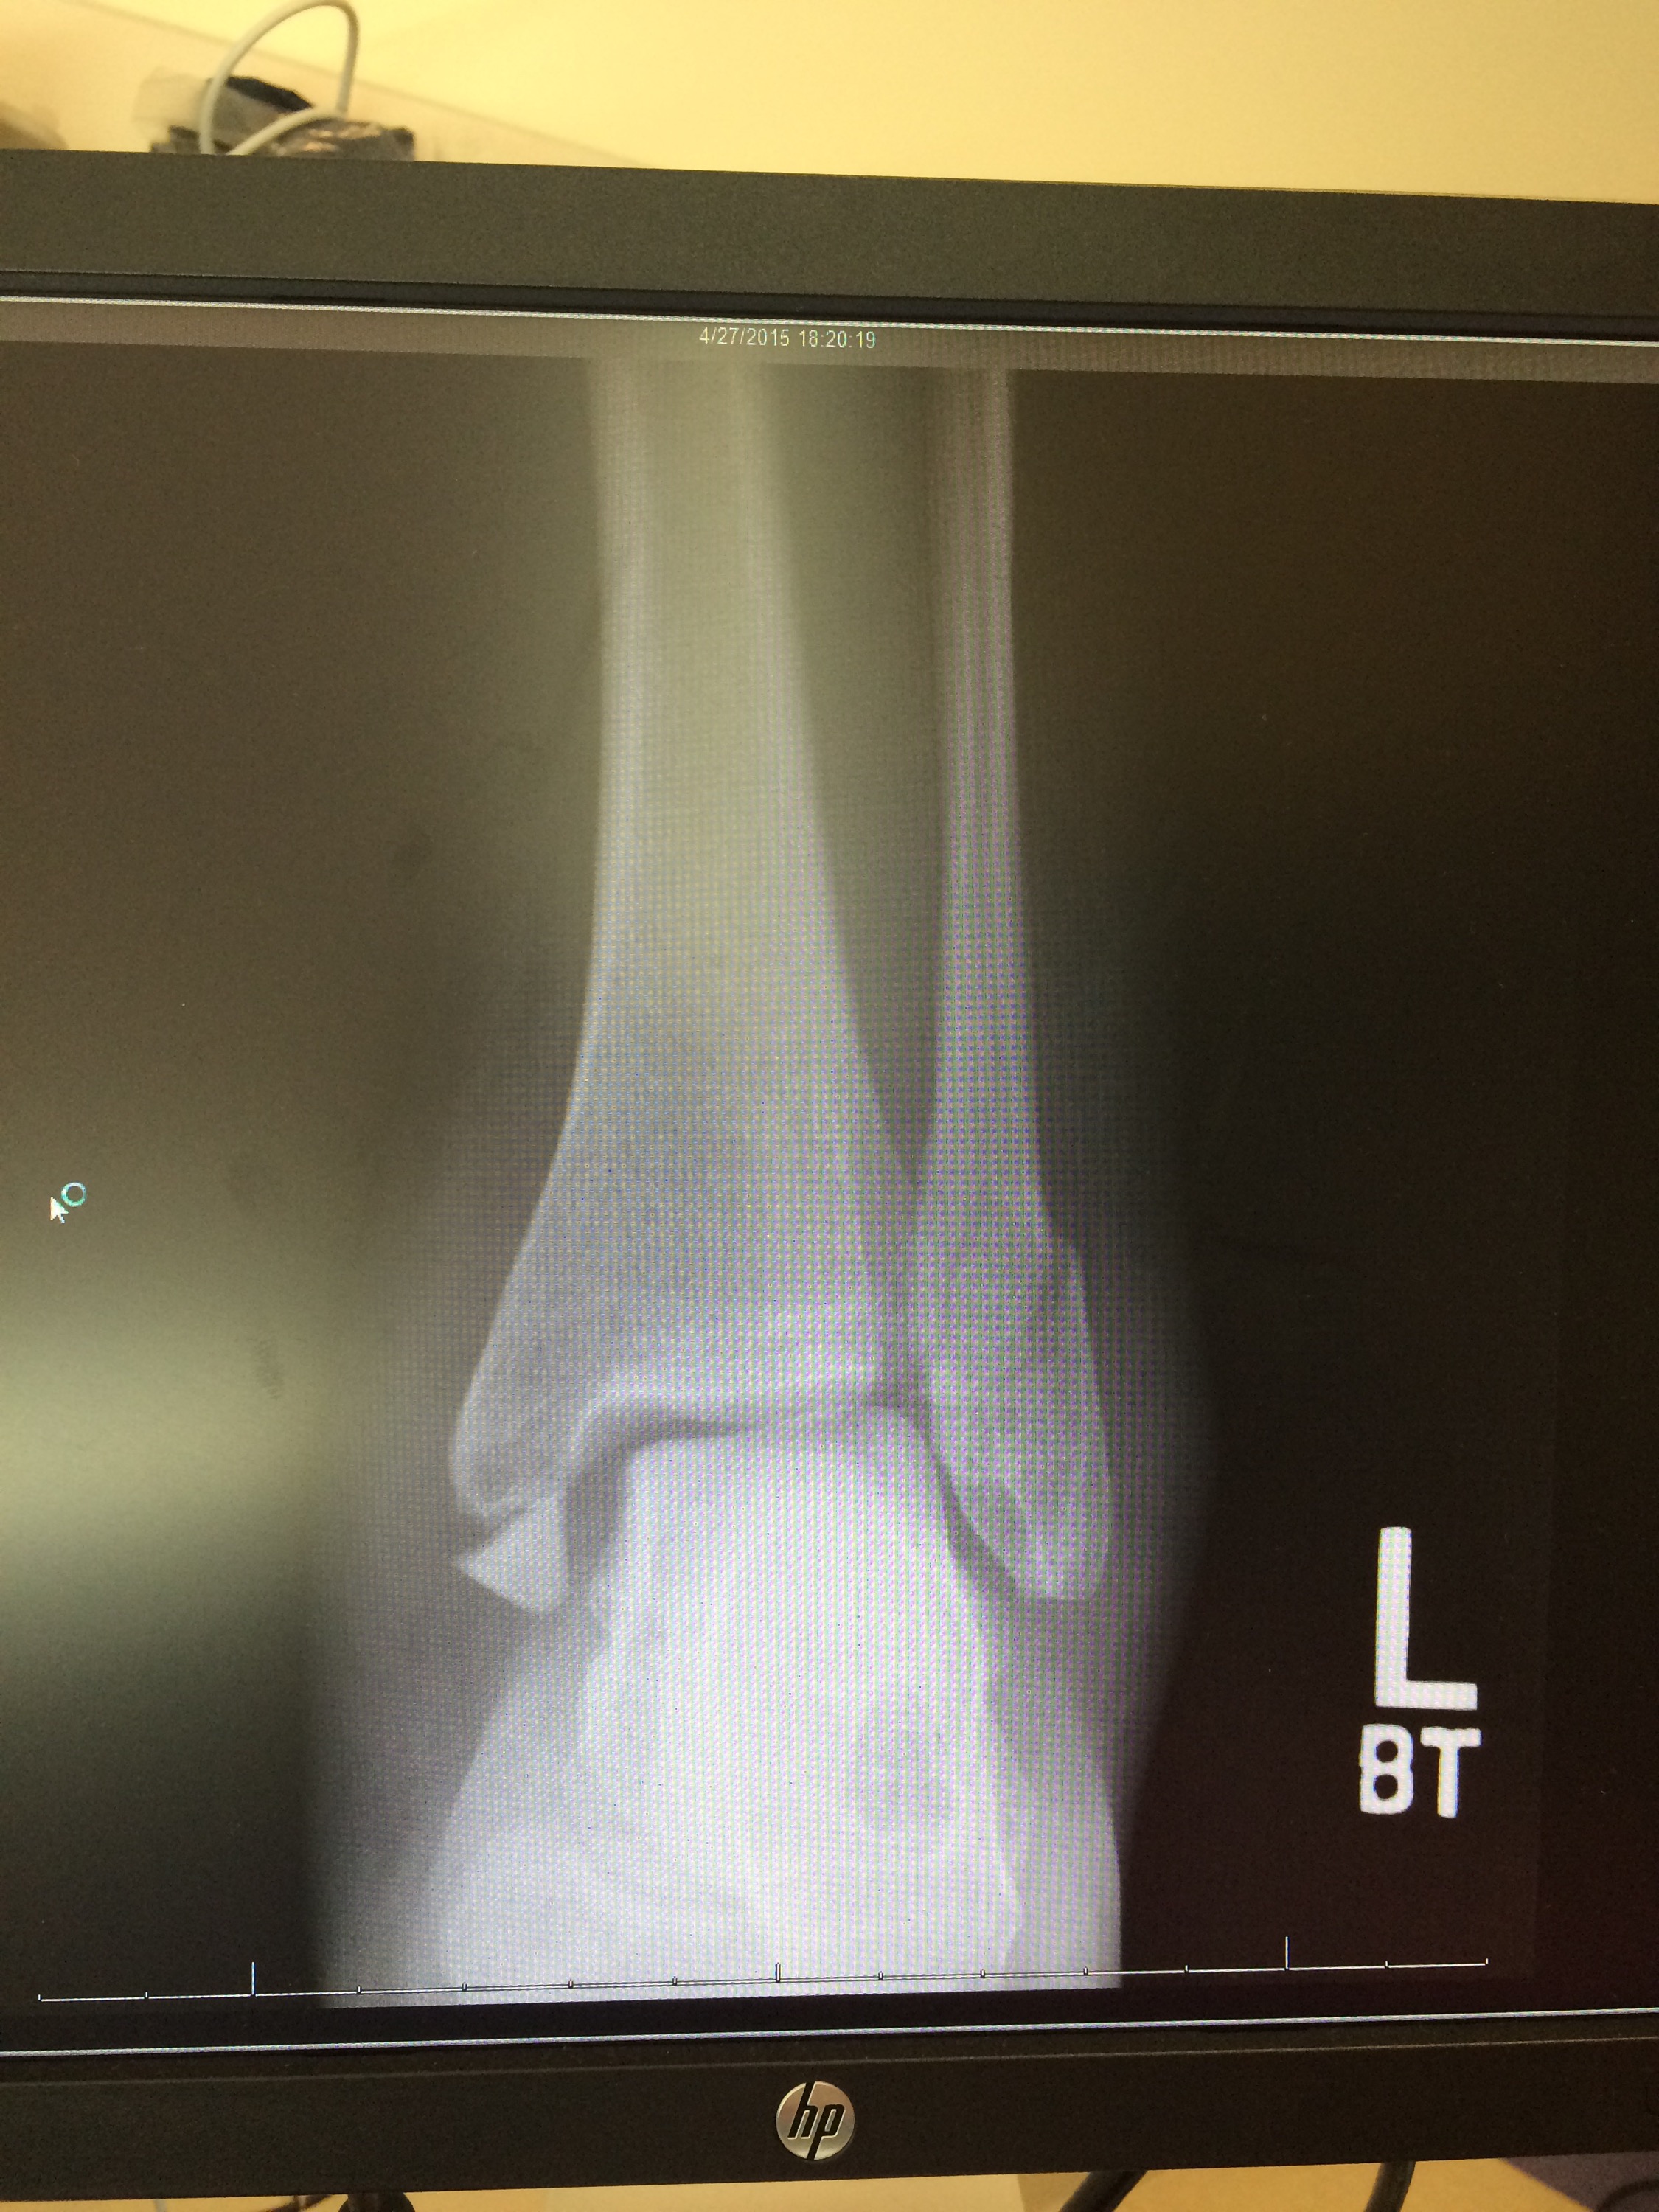

fun at the doctor…x-ray image from Monday, a new splint, kisses on each toe from my guy, and just general cuteness and love. ❤️❤️